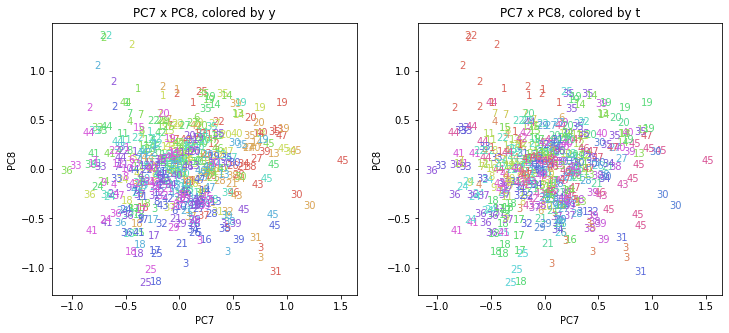

PCAの結果の第n主成分をPCnと表記します。

医療費データの場合と同様に、PCAの結果を見やすく表示するため、seabornのカラーパレットを使って、年月別、都道府県別に色分けして図示してみます(左側が年月別に色分け、右側が都道府県別に色分け)。PC1~PC8まで表示しました。

都道府県番号の表示

上の色分けだけでは都道府県が区別しにくいので、医療費データの場合と同様に、点の代わりに都道府県番号をプロットした図も描いておきます(色分けは上と同じ)。

医療費データの場合ほどはっきりとはしていませんが、PC2が概ね時間の経過を表す成分で、残りの成分が時点によって変わらない地域の特徴を表す成分となっているようです。

また、PC1×PC3を見ると、47沖縄が他の都道府県からかなり離れたところに位置しており、沖縄の地域差が際立っているのが分かります。これは、以前別の記事で年齢階級のない健診データでPCAを実行した場合と似た結果となっています。

今回は、医療費データと同様に、健診データ240次元についてPCAを実行してみました。PCAの結果、医療費データの場合ほどはっきりしとはしていませんが、第2主成分が概ね時間の経過を表す成分で、時間軸に沿った全体的な動き(全国的な動き)を表しており、それ以外の成分が地域の特徴を表す成分で、この10年間あまり変わっていないことがわかりました。